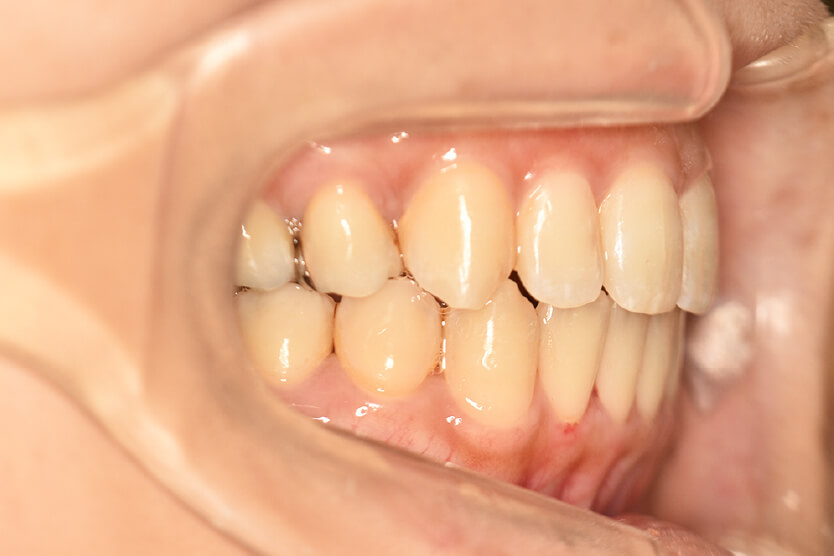

動的治療終了時

症例 症例 症例 症例

治療としては、上顎左右第一小臼歯の抜歯をし、セルフライゲーションブラケット装置(デーモンシステム)とマウスピース型矯正装置(インビザライン)で配列を行いました。

この際、上顎に歯科矯正用アンカースクリューを設置し上顎前歯部後退時の土台としました。

開咬については顎間ゴムの協力もあり改善され、口元も後退し、キレイな横顔になりました。

治療期間は2年4か月でした。